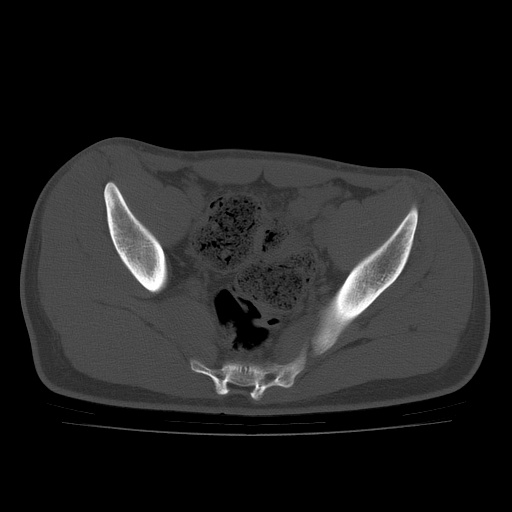

患者男性,18岁 腰腿痛1年  骶髂关节改变本人考虑强直性脊柱炎。

两侧骶髂关节骨质破坏,关节面毛糙,符合强直性脊柱炎骶髂关节改变。

符合强直性脊柱炎,虫蚀样骨质破坏。

两侧骶髂关节骨质破坏,关节面呈锯齿样改变关节间隙变窄,考虑强真性脊柱炎

双侧骶髂关节关节间隙变窄,边缘毛糙,关节面硬化,可见囊变!符合强直变现!

两侧骶髂关节骨质破坏以髂骨为主,间隙变窄,强直性脊柱炎